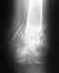

6 февраля 2011 года сломал локтевую кость со смещением. Поставили аппарат Илизарова. Вместо двух месяцев проносил четыре, срасталось медленно. Сняли, сказали разрабатывать и через 5 дней кость сместилась опять.

15 июня сделали вторую операцию, поставили дорогой стержень в кость, закрепили в области локтя на два шурупа. Перелом у меня в 1/3 ближе к кисти. Вторую часть кости одели на стержень, но не закрепляли. Также освежили концы костей, так как они зарубцевались и костномозговые каналы полностью закрылись.

Щас опять хотят загипсовать уже всю руку на 2 месяца, но мне кажется что концы костей опять зарубцевались за 2 месяца зарастания "впустую" и даже в гипсе уже не срастется.

По снимкам щель отчетливо видна. На руке вместе перелома нащупывается шишечка. Предположительно, что 1/3 кости, которая не прикручена к стержню, имеет хождение вдоль стержня.